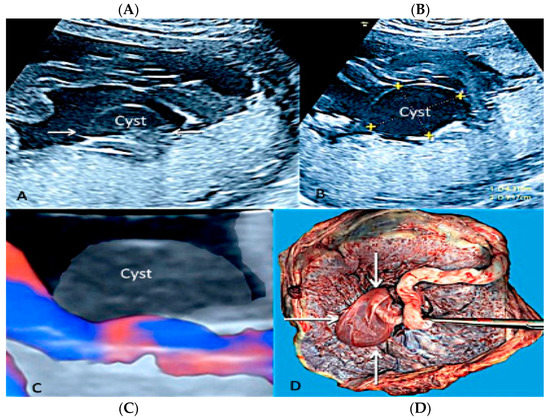

3.2.9. Umbilical Cord Cyst

3.2.10. Single Umbilical Artery